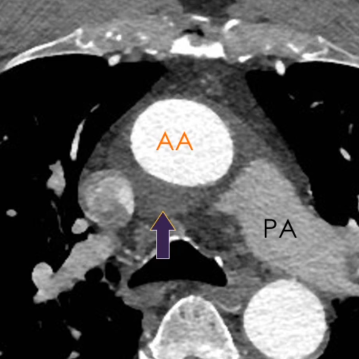

Récessus Aortique supérieur

Sinus Transverse